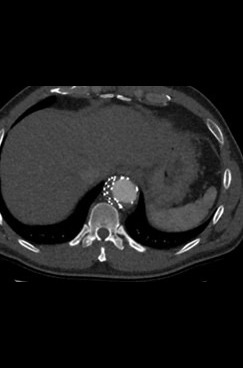

Fig. 1-4: Chronic residual type B dissection after ascending repair. Follow-up CT examination demonstrates TEVAR in descending thoracic aorta extending to the level of the celiac trunk with thrombosis of the false lumen and aortic remodeling due to FLO in false lumen. The FLO is completely collapsed in the FL due to depressurize the false lumen.